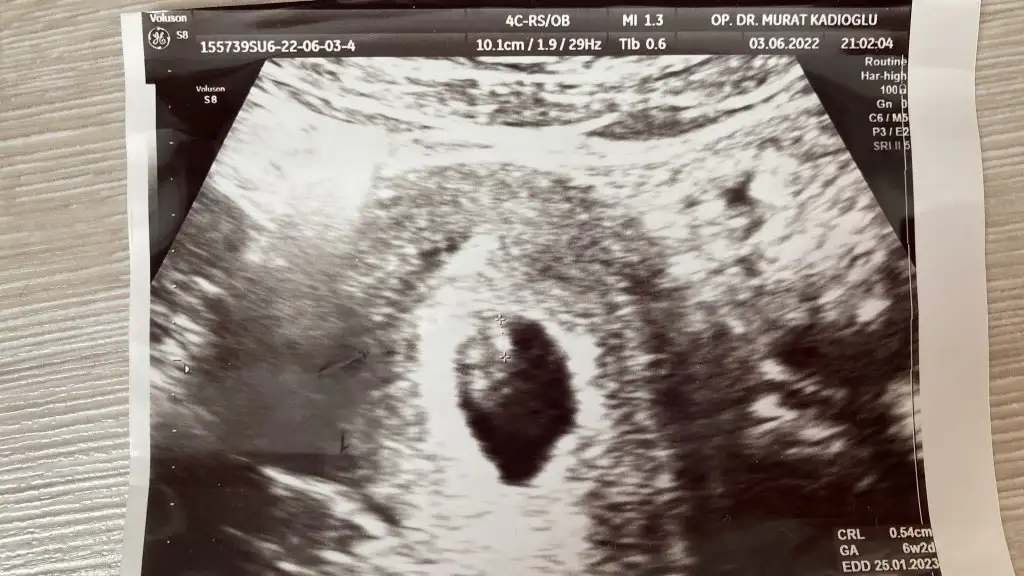

Merhaba 7 haftalık karından ultrason bizim bebeğimiz içinde tahminde bulunur musun teşekkürler

• 7 haftalık.webp

7 haftalık.webp

48,3 KB · Görüntüleme: 85